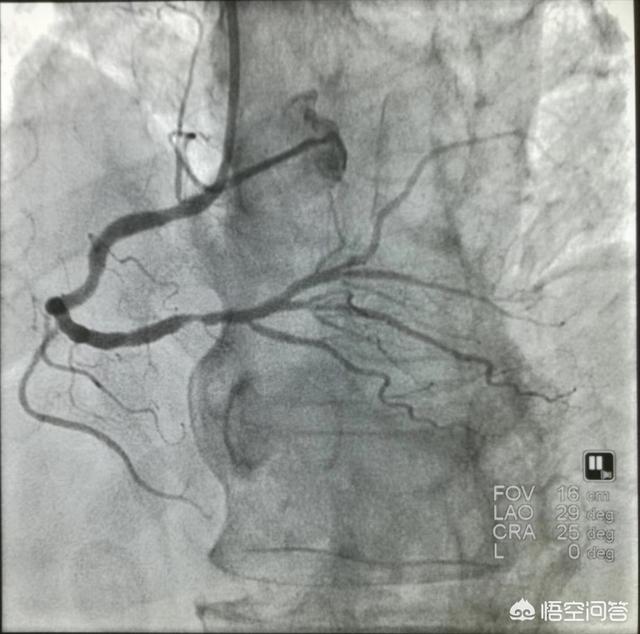

①Diagnostic clair.Le diagnostic de la maladie coronarienne n'est pas difficile à établir avec le niveau actuel des soins médicaux.coronarographieUn diagnostic définitif de la maladie coronarienne peut être posé. Un cathéter est introduit dans les artères directement jusqu'aux artères coronaires, puis un produit de contraste est libéré pour visualiser les artères coronaires, ce qui donne une image claire de l'emplacement et de l'étendue de l'obstruction, et fournit une base pour le traitement ultérieur. C'est pourquoi il s'agit également du traitement le plus courant de la maladie coronarienne.L'"étalon-or" pour le diagnostic de la maladie coronarienne.。

Le diagnostic de la maladie coronarienne est un problème systématique. Premièrement, le diagnostic de la maladie coronarienne repose sur la présence de symptômes typiques de la maladie coronarienne. Si le patient présente une oppression thoracique et un essoufflement après une activité, il doit se demander s'il souffre ou non d'une maladie coronarienne. Cependant, tous les patients atteints d'une maladie coronarienne ne présentent pas des symptômes typiques, et certains d'entre eux peuvent présenter des symptômes atypiques ou aucun symptôme du tout, et ils doivent alors faire l'objet d'un examen plus approfondi afin de diagnostiquer la maladie coronarienne. Deuxièmement, le diagnostic de la maladie coronarienne dépend de l'examen pertinent des artères coronaires. L'examen des artères coronaires comprend principalement la tomodensitométrie des artères coronaires et l'angiographie coronarienne, ainsi que d'autres données d'imagerie. Bien entendu, si un diagnostic définitif de maladie coronarienne est nécessaire, une échographie cardiaque, des analyses de sang, une résonance magnétique et d'autres examens connexes sont également nécessaires pour confirmer le diagnostic de maladie coronarienne.

Bien que les symptômes d'angine de poitrine, l'élévation du taux de troponine et les modifications de l'électrocardiogramme soient utiles au dépistage de la maladie coronarienne, l'étalon-or du diagnostic de la maladie coronarienne est la coronarographie, qui est une procédure invasive mais qui joue un rôle irremplaçable dans le diagnostic de la maladie coronarienne et dans la compréhension de la sévérité de la maladie. Grâce à l'injection d'un produit de contraste, la coronarographie permet d'observer clairement le degré de rétrécissement de l'artère coronaire, et lorsque le rétrécissement de l'artère coronaire atteint 50 %, la maladie coronarienne peut être diagnostiquée. La coronarographie permet également de comprendre les parties malades et la quantité de l'artère coronaire, ce qui peut fournir des indices très précieux pour l'évaluation de l'état de la maladie. Certains d'entre vous se demandent peut-être si la maladie coronarienne peut être guérie. Avec la technologie médicale actuelle, nous ne pouvons pas guérir la maladie coronarienne. Toutefois, le risque de progression vers l'infarctus du myocarde peut être réduit par un traitement rationnel, comprenant l'application de médicaments antiagrégants plaquettaires tels que l'aspirine ou le clopidogrel, l'utilisation de médicaments stabilisant la plaque tels que les statines, etc., ainsi que des médicaments améliorant le pronostic tels que les bêtabloquants et le priligy, etc. la maladie coronarienne.